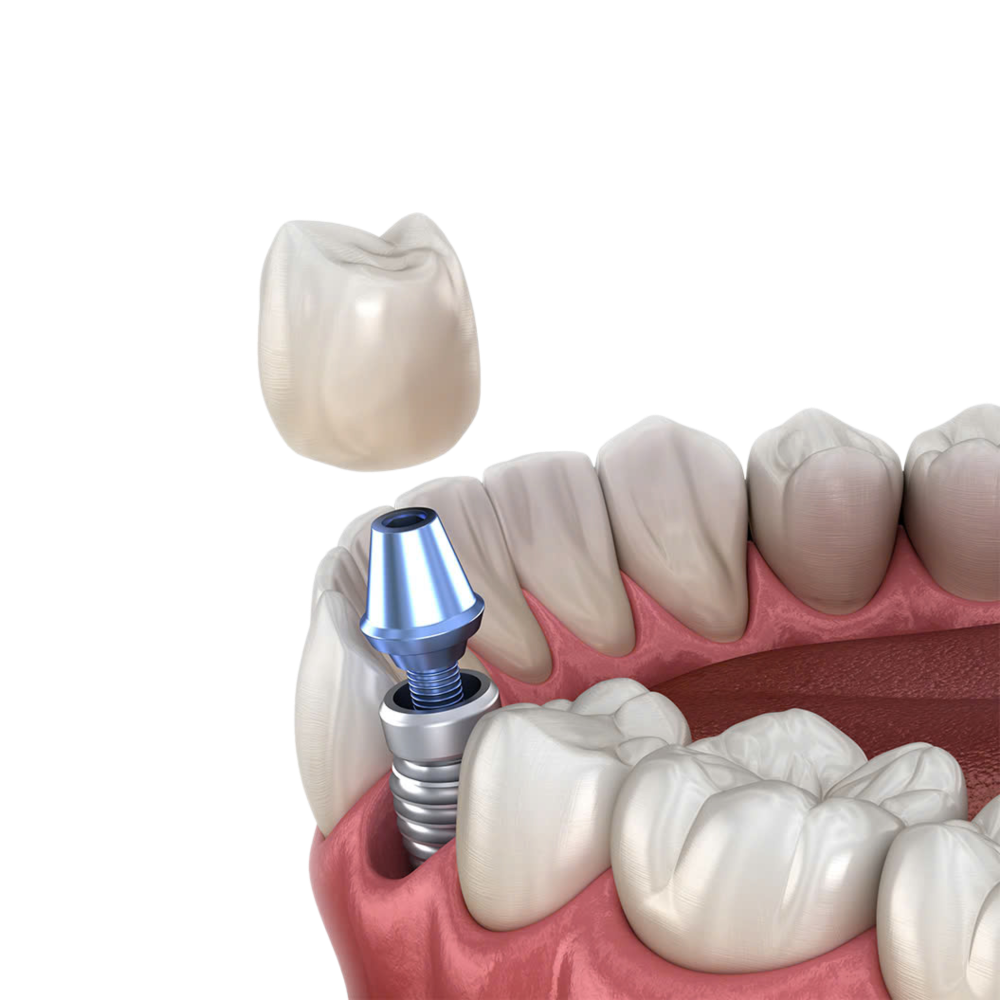

Trồng răng Implant 1 răng là phương pháp phục hồi răng mất tiên tiến, sử dụng trụ chụ chân răng nhân tạo – Implant từ titanium cấy vào xương hàm để thay thế chân răng đã mất. Sau đó, một mão răng sứ được gắn lên trụ, tạo ra chiếc răng mới với hình dáng và chức năng giống như răng thật.

- Bảo vệ răng kế cận: Không cần mài hay tác động răng bên cạnh như cầu răng sứ, giữ nguyên vẹn cấu trúc răng thật.